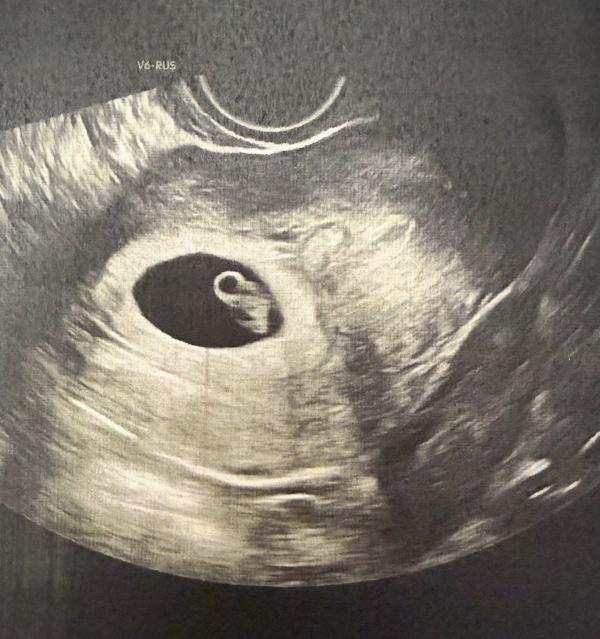

Сегодня была на плановом узи у прекрасного врача в Пятигорске Арины Арноевны🥳

6 недель и 4 дня акушерский срок

КТР малышка 10’1 👶